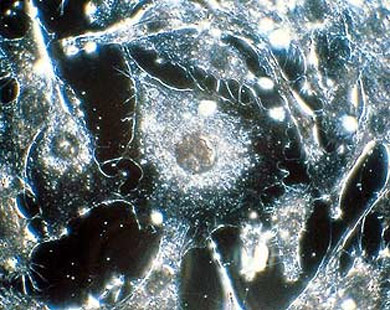

يجري تطوير مجموعة جديدة من العقاقير الطبية التي تستهدف خلايا سرطانية محدَّدة في مشروع يمنح آملا جديدا لملايين العائلات المبتلية بهذه العلة المميتة... وبعد الاختراق الوراثي الذي تحقق قبل عشر سنوات أصبح من الممكن معرفة اسرار الجينات التي تغذي السرطانات المسؤولية عن موت اكثر من 150 الف شخص سنويا في بريطانيا على سبيل المثال.

وقال البروفيسور غلام مفتي الخبير بسرطان الدم في جامعة لندن ان فهم الهندسة الوراثية للسرطان سيؤدي قريبا الى

علاجات جديدة أدق استهدافا للخلايا الخبيثة. واعرب عن اقتناعه بأن العلاجات الدوائية ستكون متاحة في غضون العقد المقبل إذا استمر التقدم بوتيرته الحالية.

ونقلت صحيفة الديلي اكسبريس عن البروفيسور مفتي ان معرفة الآليات الوراثية للسرطانات تتواصل متسارعة وستتوفر عما قريب قاعدة بيانية للطفرات الوراثية والسرطان المرتبط بكل طفرة منها. ويمكن حينذاك استهداف هذه الطفرات باستخدام علاجات جديدة.

- ويتقدم البحث في هذا المجال بخطى حثيثة حتى ان العلماء بدأوا خلال العامين الماضيين يرسمون خرائط للعيوب الوراثية التي تحدث في أنواع معينة من الاورام.

- واكتشف العلماء ان سرطانات في أجزاء مختلفة من الجسم يمكن ان تنشأ نتيجة عيوب وراثية واحدة وبالتالي يمكن علاجها بدواء واحد. كما وجدوا ان النساء المصابات بسرطان الثدي قد تكون لديهن مسببات مختلفة للاصابة وبالتالي يحتاجن الى علاجات مختلفة.